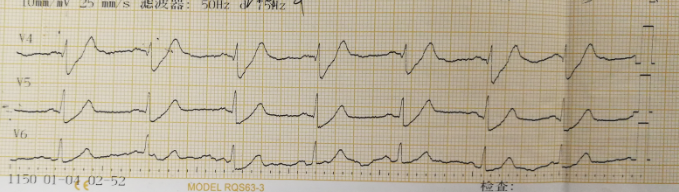

2 结果 本研究收集7例De winter综合征患者,6例进行了急诊冠脉造影,胸痛至球囊扩张平均时间为3.3 h,1例进行择期冠脉造影。其中,3例为前降支近段严重病变,1例为第一对角支闭塞,3例为前降支中段闭塞,2例合并多支血管病变,5例为单支血管病变,均行前降支支架植入术(表 4)。1周内行心脏彩超检查,4例出现室壁运动减弱,2例EF值小于50%,2例心脏形态结构未见异常,1例患者术后第2天因个人原因自动出院,未完善心脏彩超(表 5)。观察7例患者住院期间心电图演变情况,其中有3例在PCI术后出现前壁导联ST段抬高,4例未出现ST段抬高(表 5)。病例1住院期间出现室性心动过速,病例7患在急诊科就诊时发生呼吸心搏骤停,经抢救后送导管室行急诊冠脉造影。另外,所有患者经药物及介入治疗后,均症状缓解出院,院外长期服用阿司匹林100 mg/d+替格瑞洛90 mg/12 h+阿托伐他汀40 mg/瑞舒伐他汀20 mg等药物,出院1个月后电话随访,7例患者均无胸痛、气促发作及再住院,无死亡病例。

表 5 7例患者的心电图演变及心脏彩超结果

否(图 1~2) |

3 讨论 De winter综合征是近10年来新发现的心电图诊断,其诊断标准为:⑴胸前导联T波高尖对称; ⑵胸前V1-6导联J点压低1~3 mm,ST段呈上斜型下移; ⑶QRS波群通常不增宽或轻度增宽; ⑷可出现胸前导联R波递增不良; 大多数患者aVR导联ST段抬高1~2 mm。当然,这仅是心电图诊断,具体还要结合临床及其他辅助检查。目前其已被证实与前降支急性闭塞有关,占急性前壁心肌梗死的2%。虽然De winter综合征不属于STEMI范畴,但因其心血管事件的发生风险较高,有学者提出,其治疗时机应参照STEMI,尽早行冠脉造影及干预靶血管,改善预后。本文7例De winter综合征病例中,6例患者行急诊冠脉造影+PCI术,术后心脏彩超证实4例患者心功能恢复良好,1例(病例1)心脏收缩功能受到影响(EF 35%),恰巧该患者PCI术后心电图也演变为STEMI,是否演变为STEMI的De winter综合征患者的心功能较未演变为STEMI的患者更容易受损,有待于进一步证实。1例(病例5)择期冠脉造影+PCI术患者心功能明显受损,这可能与缺血时间长,心肌细胞损伤严重有关。另外,住院期间心血管事件发生、30 d再住院、死亡等方面,7例患者预后均良好。

De winter综合征表现为T波高尖,临床上应注意与急性心肌梗死超急性期、高钾等疾病相鉴别。有学者认为,De winter综合征不会演变成STEMI,与STEMI超急性期的鉴别关键在于密切监测心电图,如果是De winter综合征,其ST段不会抬高,而急性心肌梗死超急性期心电图会有动态演变,T波高尖之后会逐渐出现ST段抬高,R波下降甚至丢失,病理性Q波形成等特点,但这种观点与本研究观察到的情况不符,本文中病例1、病例5和病例6都观察到心电图演变为STEMI。临床上观察不到的原因可能是:⑴患者发病时间短,心电图还来不及演变为ST段抬高,就已行冠脉造影及支架植入开通血管。⑵ST段抬高可能是一过性的,开通血管后ST段又回落至基线。只有密切监测心电图,才可能真正发现问题。至于与高钾导致的T波高尖的鉴别,急查血清钾即可明确。De winter等[1]发现心电图表现为ST段上斜型压低,T波高尖的患者,冠脉造影均提示前降支近段闭塞,且为单支血管病变。本文中观察到,3例为前降支近段严重病变,1例为第一对角支闭塞,3例为前降支中段闭塞,2例合并多支血管病变,5例为单支血管病变。亦有研究发现,心电图表现为De winter综合征,但冠脉造影却提示左主干闭塞[8]。可见,本文的发现及Murat等[8]的发现提示De winter综合征的靶病变不一定局限于LAD近段。另外,从本文观察到的情况,患者发病年龄都相对年轻,且均为男性,2例合并高脂血症,与以往文献报道[9]相符。